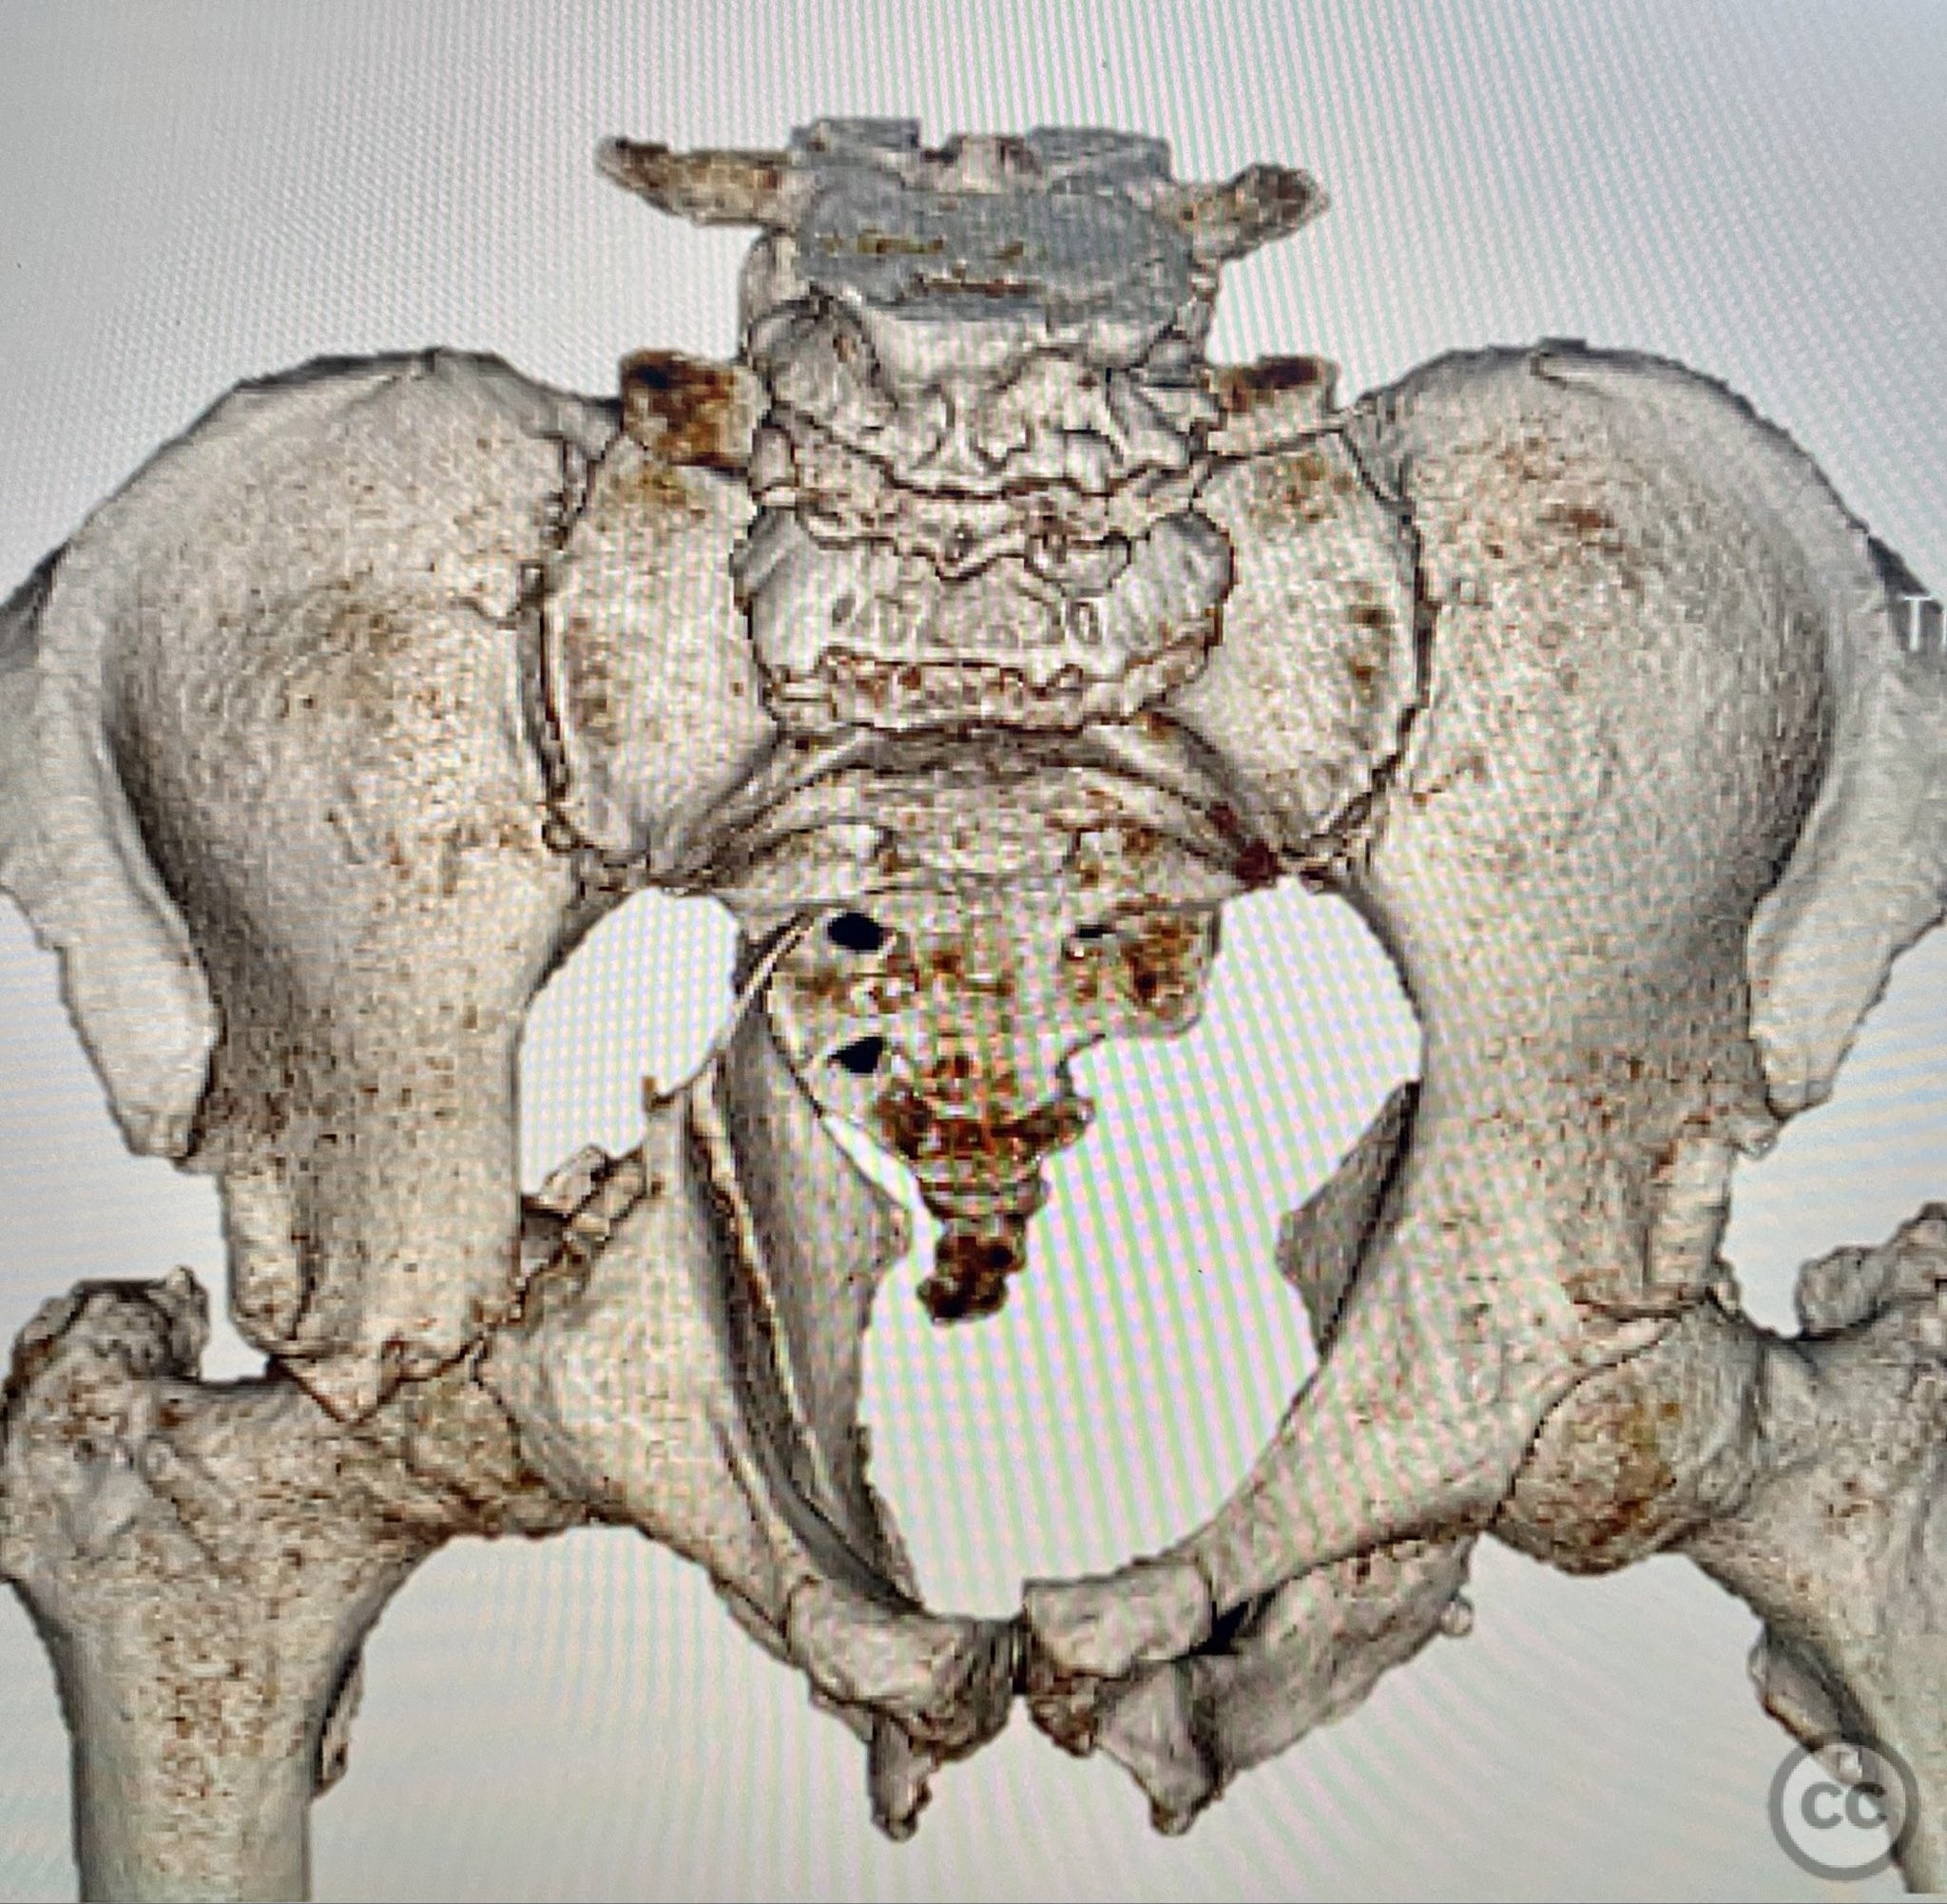

Clinical Details

Clinical and radiological findings:  A 79-year-old male sustained a high-energy injury in a motor vehicle collision, resulting in a complex acetabular fracture-dislocation. Radiographs and computed tomography demonstrated a posterior wall and transverse acetabular fracture (AO/OTA 62-B1.3), with the posterior wall fragments displaying an atypical caudal hinge configuration. The medial wall fragment was non-articular. Axial imaging revealed an impacted osteochondral fragment obstructing reduction, as well as disruption of the capsular structures adjacent to the intact articular segment. The obturator internus tendon appeared taut but intact, with no evidence of sciatic nerve impingement or superior gluteal neurovascular compromise.